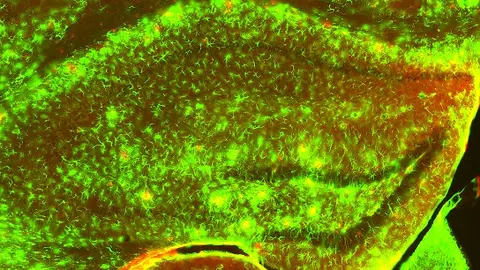

Albert Giralt, director del estudio en el que se han hallado las células que ayudan a la supervivencia de las neuronas, nos atiende en La brújula para explicarnos en qué consiste. Cuenta que "los factores neurotróficos son muy difícil de producir" y expresa que "utilizando los mismos marcadores que los astrocitos será como una terapia autoregulada".